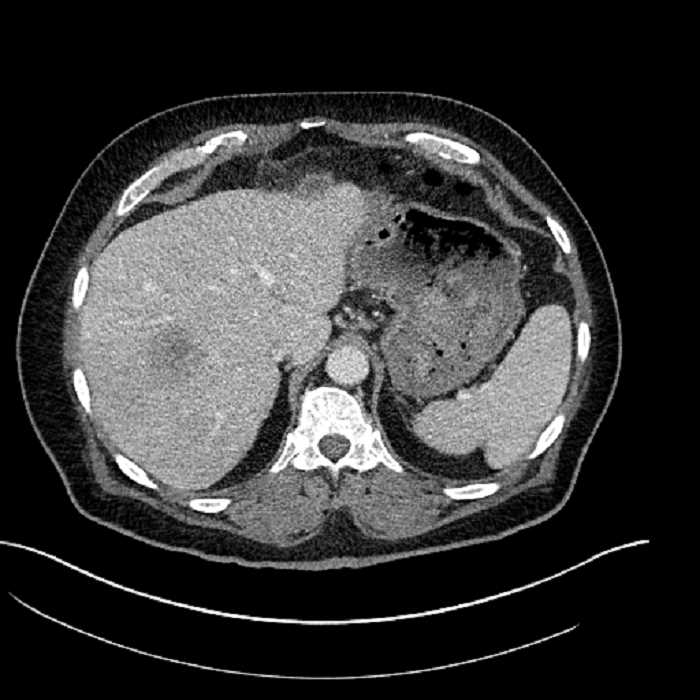

• Large fluid density structure in hepatic segments 7 and 8 measuring 10 x 7 x 7 cm with internal septation and circumferential ill-defined low density compatible with edema

• Peripherally enhancing subcapsular collections along the anterior margin of the left hepatic lobe measuring 3 x 1 cm and 2 x 1 cm

• Clearly marginated fluid density structure in segment 7 and several other scattered tiny hypodensities, which likely represent cysts

• Hepatic abscess

Acute sigmoid diverticulitis complicated by a small contained perforation and a large abscess in the right hepatic lobe. Additional small subcapsular abscesses along the anterior margin of the left hepatic lobe.

• The classic CT imaging appearance is a double target sign with internal low density surrounded by an internal enhancing rim (capsule) and a low density external rim (edema)

• Abscesses may be unilocular or multilocular

• Gas is present in a minority of cases

• Unfortunately, necrotic tumors can have an overlapping imaging appearance, so it is important to follow these to resolution

Hepatic abscess showing the double target sign with low density internally surrounded by a thin inner enhancing rim (red arrow) and ill-defined outer low density rim (yellow arrow). Blue arrow indicates an internal septation. Red arrows: additional smaller subcapsular abscesses. Red arrow: focal contained perforation associated with diverticulitis.